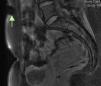

A 32-year-old woman on follow-up in gastroenterology outpatients for ileocolic Crohn disease had started to experience cyclic abdominal pain, with appearance of a mass close to the scar resulting from a cesarean section performed 10 years previously. Abdominal ultrasound showed a 4.7cm×3cm solid lesion inside the right anterior rectus abdominis muscle, hypoechoic with respect to the muscle and with no flow on colour Doppler imaging, in addition to 3 cystic lesions on its periphery (Figs. 1 and 2). All findings were suggestive of endometrioma. Magnetic resonance imaging (MRI) requested for better characterisation showed the lesion to be T1-hypointense relative to surrounding muscle, containing hyperintense foci on fat-suppressed T1-weighted images, suggestive of haemorrhagic foci (Figs. 3 and 4). Ultrasound-guided fine needle aspiration (FNA) found cytology consistent with endometriosis. As the patient was asymptomatic and did not wish to undergo surgery, it was initially decided to monitor the lesion by ultrasound. She is currently receiving only analgesic treatment on demand, with which she controls the cyclic episodes of abdominal pain. The lesion has remained stable in the follow-up ultrasounds, and comparable to the size at diagnosis.

Endometriomas of the anterior abdominal wall are chiefly diagnosed by ultrasound or MRI.6 Their ultrasound characteristics are a hypoechoic, heterogeneous mass, with internal echoes, more rarely solid or even with cystic changes (pools of blood secondary to a recent bleed). They are usually accompanied by a hyperechoic halo due to inflammation of the surrounding tissue.4,5 Colour Doppler shows a vascular pedicle at the periphery, with low intralesional signal intensity.7 The lesion appears as a solid mass on computed tomography (CT), isodense relative to muscle, while on MRI it appears as isointense to muscle on T1-weighted images and as high signal intensity on T2-weighted images, both with contrast uptake in the arterial phase.5 All these features are very non-specific for making a correct preoperative diagnosis, which is only achieved in 20–50% of cases,4,5,7 probably due to low clinical suspicion due to the non-specific nature of the symptoms, and their late development (between 2 and 5 years after the surgery).2,3,5,7 Ultrasound-guided FNA is the first approach to determine the nature of the lesion. It is limited by the scant cellularity in cystic or bleeding lesions, which is insufficient for a correct histological diagnosis, as well as the frequent atypia of the glandular cells, which makes differential diagnosis difficult. The presence of 2 of the 3 typical components (endometrial glandular cells, stromal cells or macrophages with haemosiderin) confirms the diagnosis of endometriosis by FNA.8,9 Its use is still not clear due to the risk of creating new implants.4 CA-125 determination is not recommended owing to its low sensitivity.1,7